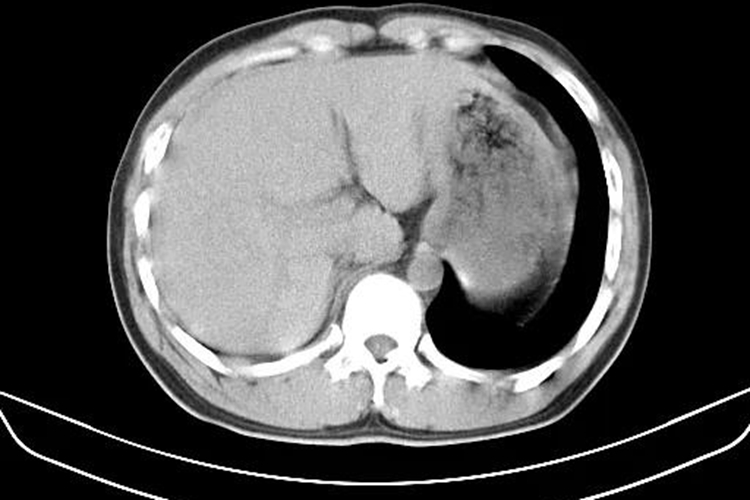

肝破裂多由坠落、机械性损伤导致,CT影像表现为肝实质破裂、肝血肿等,根据破裂的范围以及血肿的情况可分为Ⅰ-Ⅵ级。

肝破裂的CT影像主要表现为肝实质损伤、破裂,以及肝出血导致血肿,根据损伤范围不同可分为Ⅰ-Ⅵ级,级别越低,损伤程度越低,例如Ⅰ级血肿小于1%的肝表面积,肝被膜撕裂,肝实质破裂深度小于1cm,而V级或Ⅵ级时肝实质破裂超过75%肝叶,肝脏从肝蒂上撕脱。